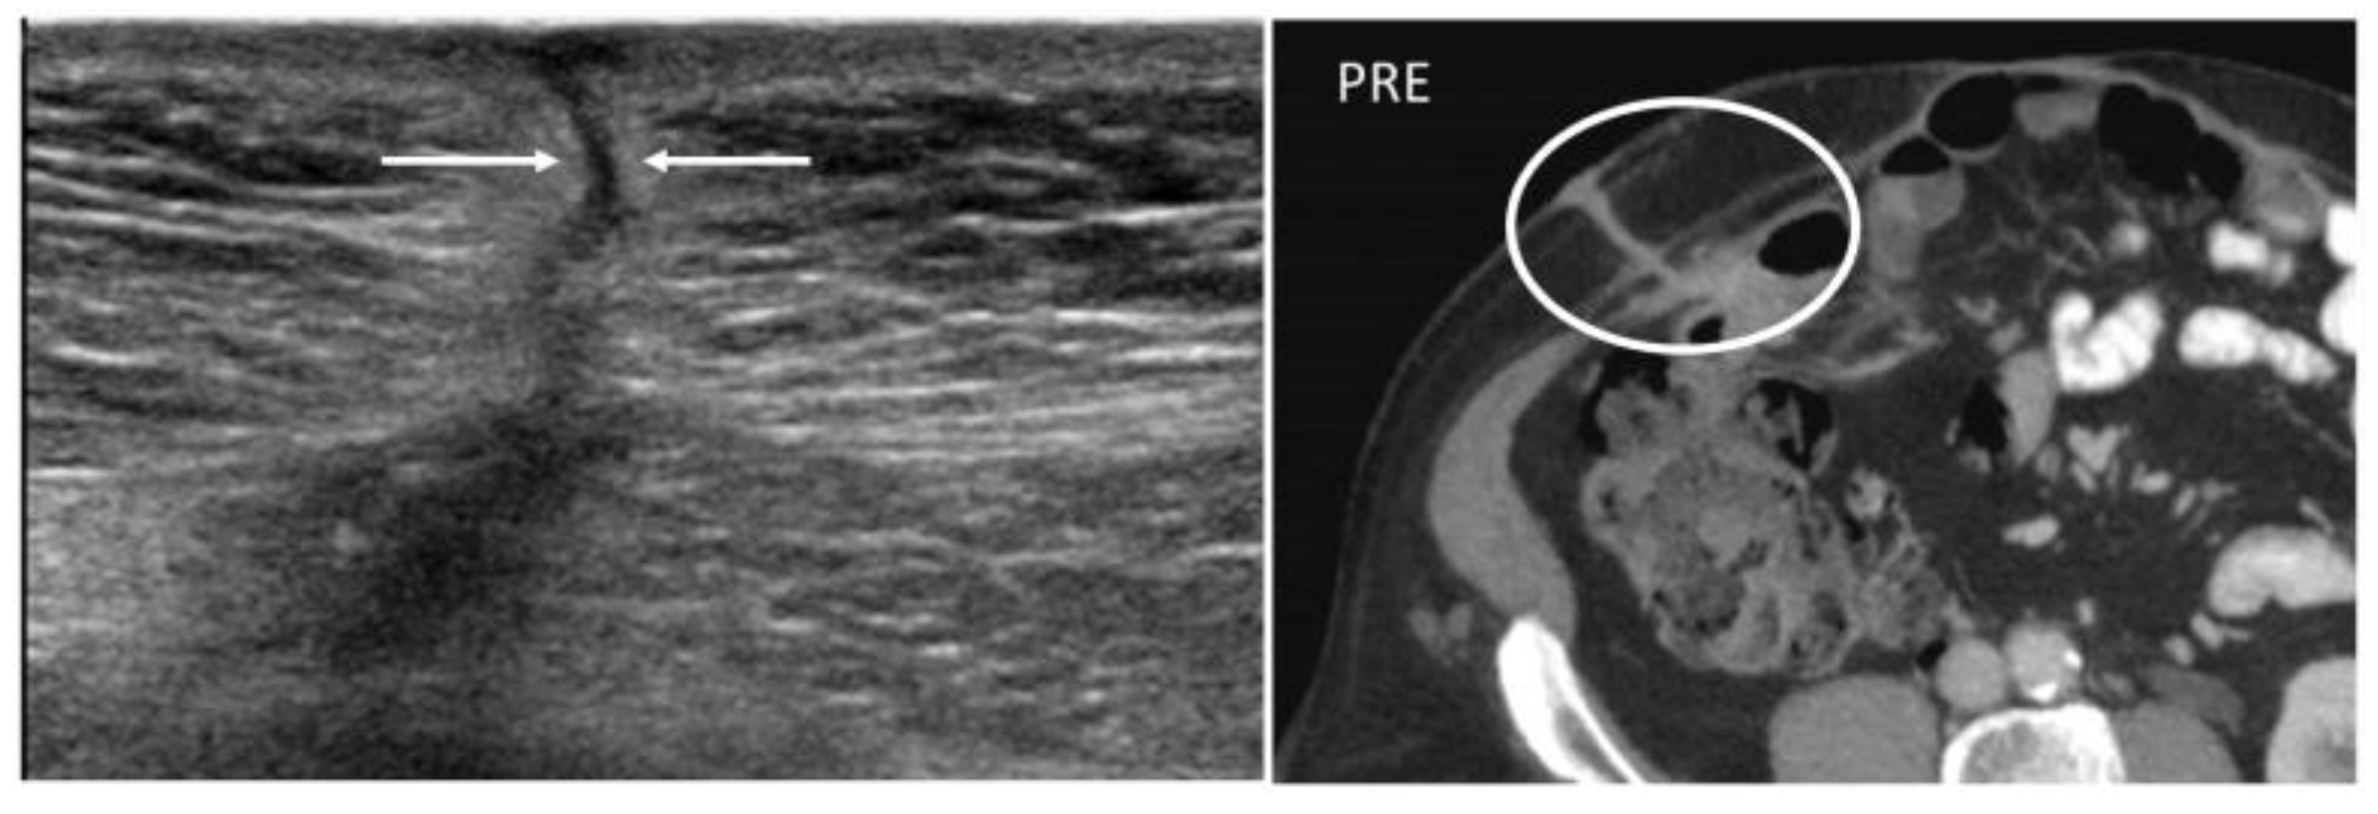

Abdominal wall abscesses present on US as superficial fluid-filled complex lesions, with ill-defined margins, predominantly hypoechoic to surrounding muscles [7,8]. Peripheral hyperemia can be seen on Color Doppler US (CDUS) [3] (Figure 1). To define the extent of the abscess, contrast-enhanced CT and MR could be used in severe cases.

Figure 4. A 22-year-old man with reactivation of Crohn’s disease, presenting as a new enterocutaneous fistula. B-mode US with linear transducer (first picture) shows the presence of a fistulous trait between the skin and a superficial collection (arrows). Axial not-enhanced CT scan (second picture) revealed the course of the fistula, demonstrating communication between the bowel loops and the skin, together with a small collection (circle).